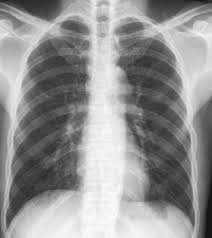

Legionellose Radio Pulmonaire - Https Www Orpha Net Data Patho Pro Fr Legionellose Frfrpro815 Pdf - Tous les décès depuis 1970, évolution de l'espérance de vie en france, par département, commune, prénom et nom de famille !. Face aux symptômes qui évoquent une pneumopathie interstitielle, le médecin va tout d'abord prescrire une radio des poumons, qui met en évidence un épaississement du tissu interstitiel. Oct 13, 2020 · l'emphysème pulmonaire existe sous différentes formes. Tous les décès depuis 1970, évolution de l'espérance de vie en france, par département, commune, prénom et nom de famille ! Il peut être localisé à une partie du poumon ou s'étendre à l'ensemble de l'appareil pulmonaire.